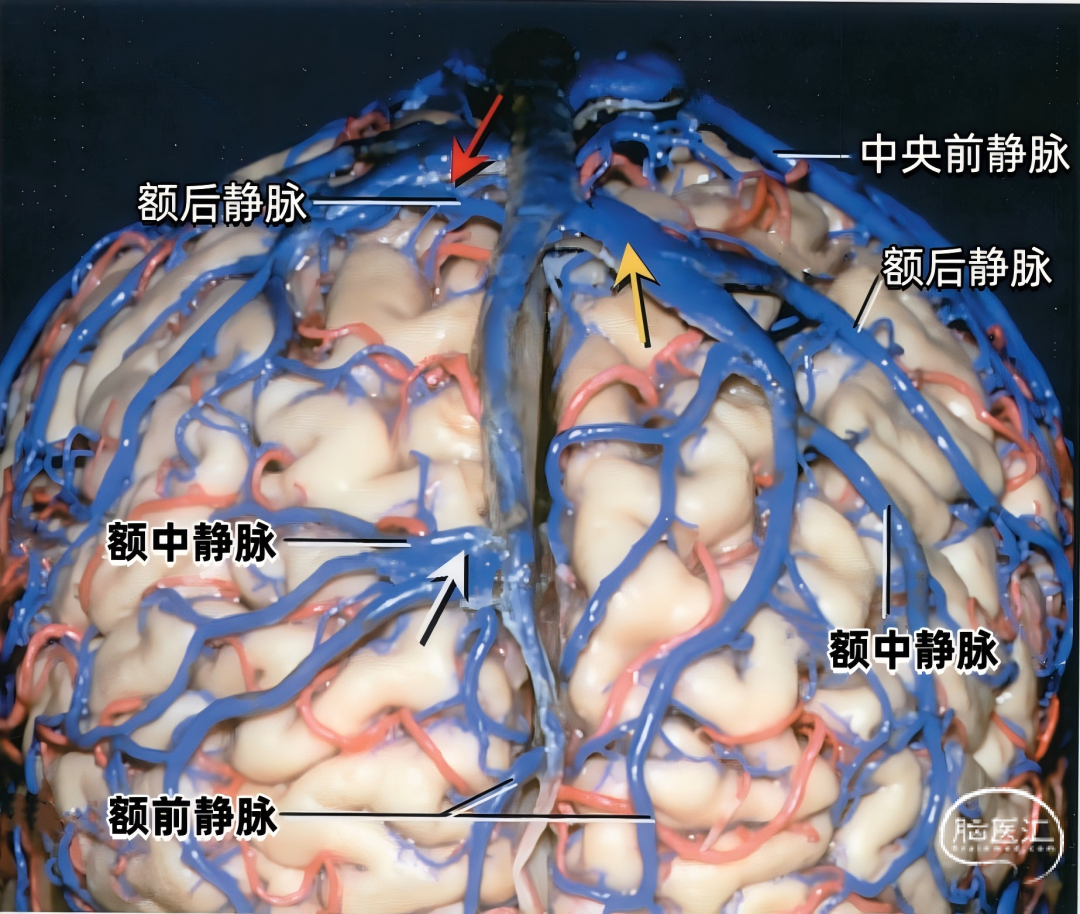

从两侧皮层汇入上矢状窦的皮层静脉具有特有的形态(下图)。左侧显示汇入上矢状窦的静脉,右侧显示静脉入窦的平均角度。从前到后,静脉入窦的角度逐渐减小。 额极附近的静脉,与上矢状窦内血流方向一致,汇入上矢状窦; 额叶后部的静脉向前汇入上矢状窦,与窦内血流的方向相反; 顶叶和枕叶的静脉向前汇入上矢状窦,与窦内血流方向相反;| 额极静脉 110° | 额前静脉 110° |

| 额中静脉 85° | 额后静脉 65° |

| 中央前静脉 50° | 中央静脉 45° |

| 中央后静脉 40° | 顶前静脉 25° |

| 顶后静脉 15° | 枕静脉10° |

下图示右侧额中静脉、额后静脉先进入靠近上矢状窦的硬膜窦。然后再进入矢状窦。额前静脉直接引流入上矢状窦。黄色箭头所指为硬膜窦,右侧有2个,左侧有3个。

下图示左侧额前、额中,额后静脉和中央前静脉不直接进入上矢状窦,而是进入额叶上缘的硬膜窦,然后进入上矢状窦。黄色箭头指示左侧的4个硬膜窦。